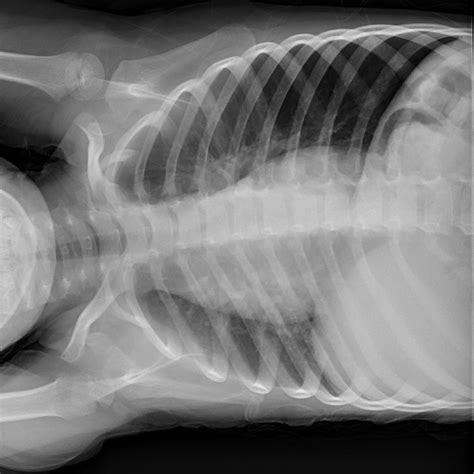

Right Lateral Decubitus

The Right Lateral Decubitus position is defined by the patient resting their right side against the examination table or bed. This positioning is not merely about comfort; it is a calculated maneuver to shift internal contents. When a patient is placed in the RLD position, organs such as the heart, lungs, and abdominal viscera shift according to gravitational forces. This effect is frequently utilized in diagnostic imaging—such as X-rays, CT scans, and echocardiograms—to differentiate between air-fluid levels or to move bowel gas away from a specific region of interest.

• Radiographic Imaging: It is frequently used in chest X-rays to detect small amounts of pleural effusion or pneumothorax that might not be visible in an upright or supine position.

When performing imaging in the Right Lateral Decubitus position, technicians must be precise with beam angulation and patient orientation. If the goal is to detect a pleural effusion, the patient is placed so that the side being examined is the "down" side. This allows the fluid to gravitate to the dependent portion of the thoracic cavity, where it is more easily identified against the chest wall. Conversely, if searching for free intraperitoneal air (pneumoperitoneum), the patient is often placed so that the potential air space is at the highest point.